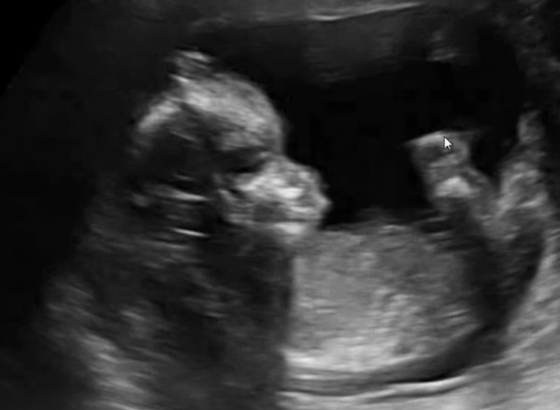

아가의 심정지와 함께 멈춰버린 내 시간은 긴 시간 동안 당신을 힘들게 했던 것 같아.

어두운 병실에서 심장이 멈춘 울지 않는 아이의 분만을 기다리며 새로 태어나는 아이들의 울음소리 속에 함께 잠을 청하던 일.